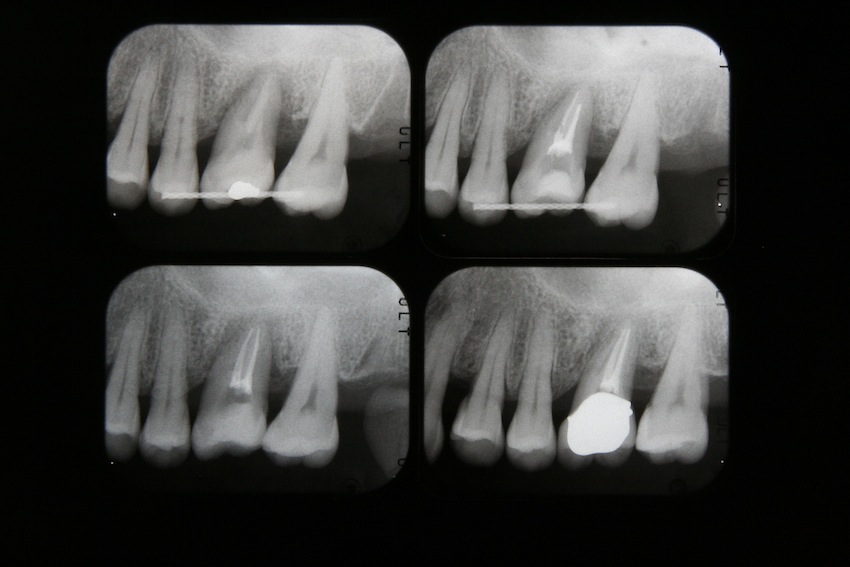

写真3 レントゲンの経過です。右下が治療後です。非常に安定したいい状態です。